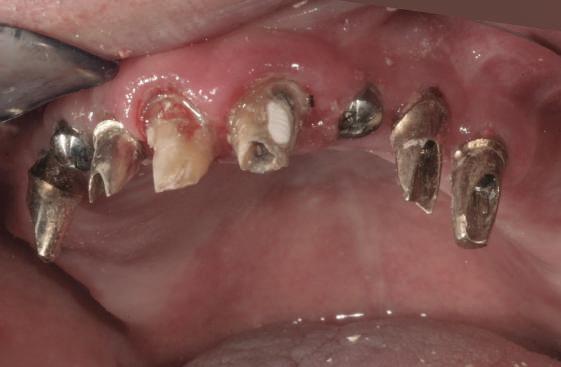

Reabilitările implantare complexe pot include abordări în etape, implicând de obicei extracţia seriată a dinţilor irecuperabili. Se evită astfel necesitatea protezelor mobilizabile prin menţinerea dinţilor naturali în cursul vindecării şi împiedică încărcarea imediată a implanturilor plasate în osul grefat. Un dezavantaj major constă în recesia gingivală. Acest articol dezbate diverse abordări pentru gestionarea modificărilor gingivale şi sugerează modificări de protocol în cursul fazei de planificare terapeutică cu implanturi.

Pla una susţinută de implanturi pot fi îndelungate atunci când obiectivul constă în evitarea aplicării unei proteze mobilizabile. Una dintre opţiuni este reprezentată de încărcarea imediată a implanturilor cu o restaurare totală provizorie. Când acest lucru nu este posibil, trebuie implicate metodologii pentru evitarea încărcării imediate. Mulţi dentişti restauratori şi chirurgi orali pot opta atunci pentru extracţiile seriate, astfel încât pacientul să nu rămână deloc fără dinţi. Acest protocol, denumit adesea abordare stadializată, protocol de extracţie în serie sau tratament multifazic a fost formulat

Deşi poate varia de la pacient la altul, acest tip de tratament implică de obicei stadii multiple de inserare a implanturilor în cursul cărora dinţii reziduali dar irecuperabili sunt menţinuţi ca bonturi temporare pentru a susţine restaurări provizorii fixe. Odată cu realizarea conexiunii dintre bonturi şi primul set de implanturi, dinţii reziduali se extrag şi se efectuează o a doua etapă de inserţie a implanturilor. După vindecarea celui de-al doilea set sau a setului final de implanturi, se pot realiza procedurile protetice pe implanturi pentru a finaliza terapia. Cavallaro & Greenstein au împărţit acest protocol în două clasificări: clasa I, cu toate implanturile inserate în cursul primei etape chirurgicale; şi clasa a II-a cu două sau mai multe etape de inserare a implanturilor pentru a genera suficientă susţinere implantară.

Dacă planul de tratament etapizat are una, două sau mai multe faze implantare, principalele dezavantaje ţin de

durata tratamentului şi implicarea mai multor etape chirurgicale. Avantajele sunt numeroase, incluzând: abilitatea de a utiliza o restaurare provizorie fixă pe toată durata tratamentului şi a fazelor de vindecare, ghidajul simplificat pentru inserarea implanturilor, menţinerea funcţiei masticatorii şi managementul ţesutului moale. În pofida progreselor precum planificarea virtuală, încărcarea imediată şi suprafeţele îmbunătăţite ale corpurilor implantare, vindecarea ţesutului moale nu este încă predictibilă în mod curent. Deşi pierderea de până la 1mm din osul marginal în cursul primului an după conexiunea bontului era acceptabilă odinioară, a devenit evident că aceasta poate însemna totodată pierderea de ţesut moale în aceeaşi perioadă sau în anii următori. Indiferent că pierderea tisulară este imediată sau ulterioară, succesul tratamentului este judecat din prisma funcţiei şi a esteticii dentare dar şi a ţesutului moale.

Managementul ţesutului moale în abordarea etapizată poate fi imprevizibil şi prezintă provocări estetice, în principal recesia gingivală.

Acest articol va prezenta câteva exemple de cazuri cu abordare etapizată în cazul unor recesii de ţesut moale în jurul bonturilor.

Cazurile sunt organizate prin modificări ale planului de tratament, care variază de la menţinerea gulerului auriu vizibil al bontului şi până la refacerea bonturilor şi a elementelor turnate.

Cazul (1)

Reprepararea intraorală a bonturilor Acest pacient prezenta dentiţia maxilară compromisă, refuzând proteza mobilizabilă. Prin abordarea în etape, se menţin o parte din bonturile dentare naturale; s-a observat recesie în momentul amprentării pentru cel de-al doilea grup de implanturi.